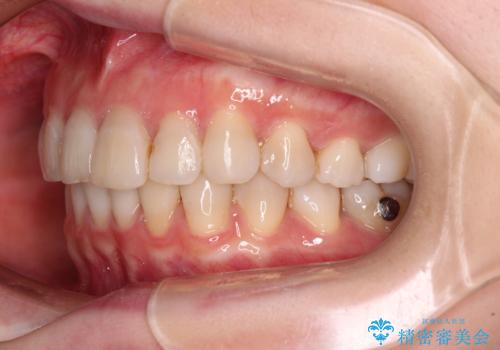

前歯の突出感とデコボコをインビザライン矯正で改善

- 上下前歯の突出感とデコボコを気にして来院された患者様です。

インビザラインによる上下歯列の側方拡大と後方移動、IPR(歯と歯の間を削る)にるスペースの獲得により歯列を整えることとしました。

骨格的な左右差があったため、上下の正中を合わせることができませんでした。

骨格の差は改善できないため、奥歯の咬み合わせに物足りなさを感じましたが、奥歯の咬み合わせによる不自由はなく、口元の突出感も改善することができました。